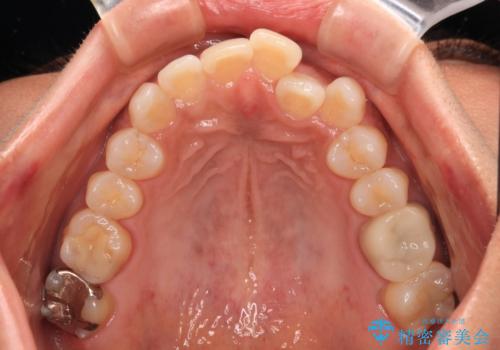

クロスバイトを治したい インビザラインによる矯正治療

- 前歯のクロスバイトを気にして来院された患者様です。

上下ともに、前歯部を中心にやや叢生が認められる程度であったため、ワイヤーでもインビザラインでも、どちらでも対応可能な状態でした。

咬合力が非常に強く、治療が進むにつれて上下奥歯が離開してくることが予想されるため、治療途中から上下の顎間ゴムを使用することを理解いただき、インビザラインによる矯正治療を行うこととしました。

咬合力による臼歯離開は顎間ゴムで改善されましたが、それとは別に下顎小臼歯がマウスピースに追従せず、補正のためのゴムかけが必要となりました。

大変なゴムかけ作業を頑張っていただき、無事に治療を終えることができました。